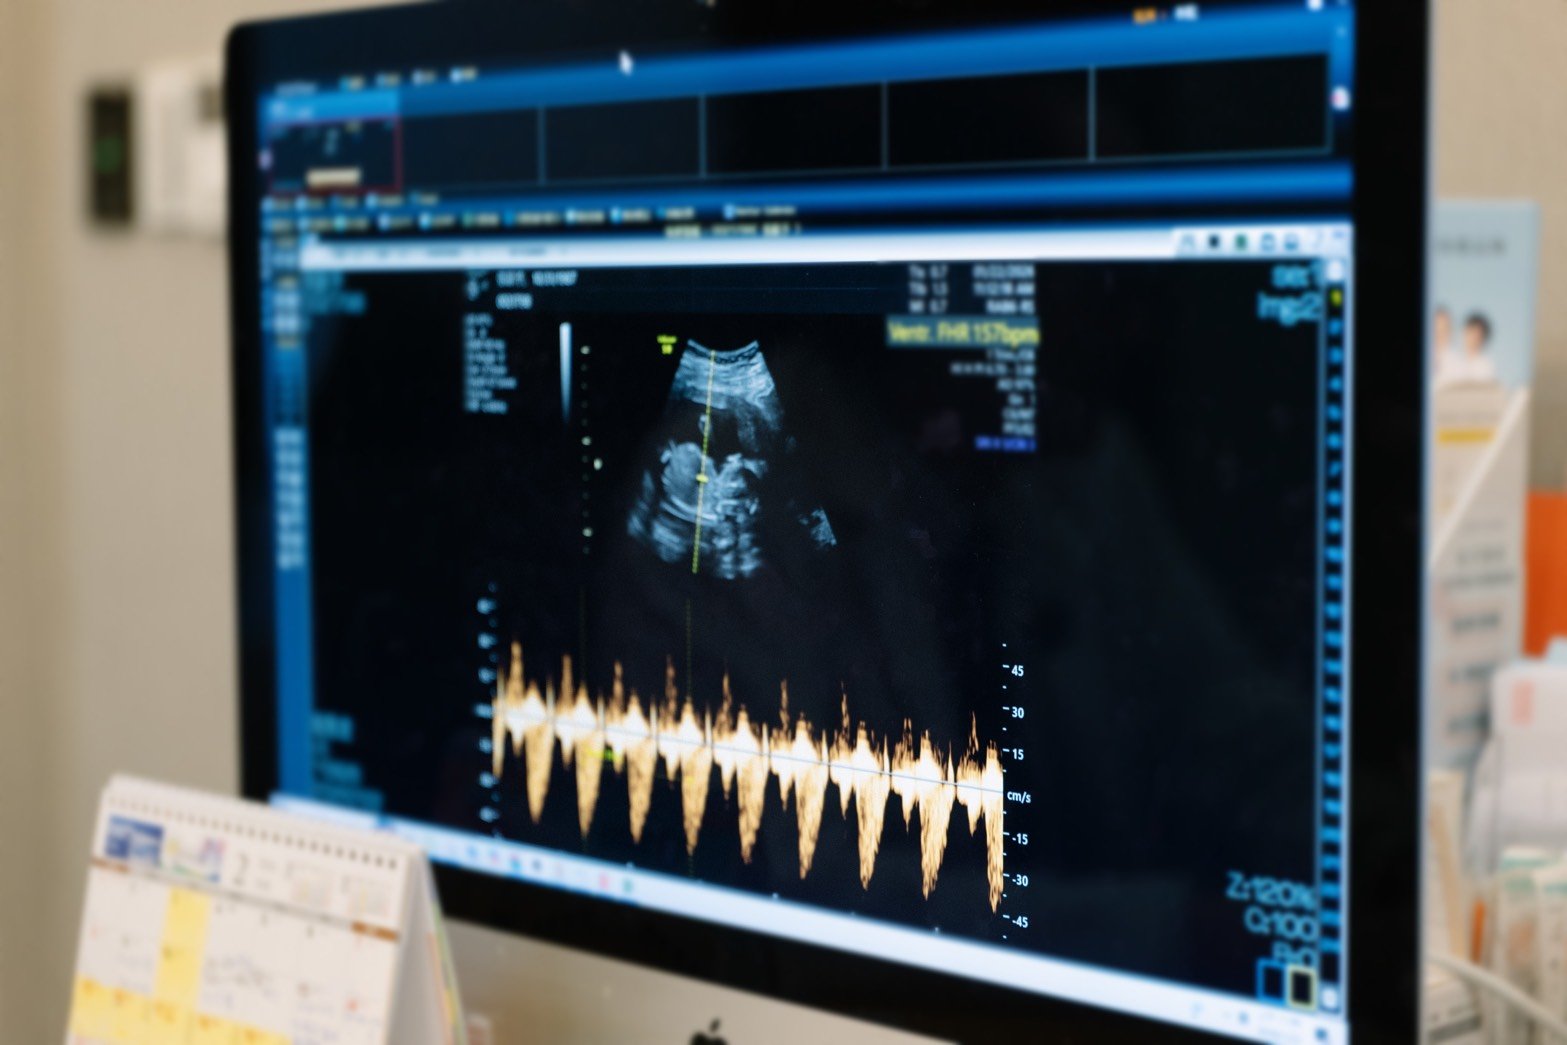

曾啟瑞醫師說明,PGS(胚胎植入前染色體篩檢)是在胚胎植入前,透過切片技術檢測其染色體是否正常,過程僅選取未來發育為胎盤的「滋養層」細胞,不會傷及發育為胎兒的「內細胞群」,好像從一顆樹的許多樹根中取樣,不影響整棵樹的生長。儘管PGS為目前臨床最先進的篩檢技術,但仍有 20% 的機率可能存在微小瑕疵或不著床,這是目前全球醫學無法完全排除的限制。

曾啟瑞醫師指出,試管療程的成功與否並非單一因素決定,即使是經過PGS判斷為正常的胚胎,在臨床上仍可能受到個體差異影響,而出現未能著床的情況,尤其是胚胎正常率會隨年齡增長而遽降,根據1,800 個切片案例研究顯示,超過40歲的胚胎正常率僅剩 15%。

因此,臨床上會在基於既有條件,進一步釐清可能影響懷孕結果的原因;為使張齡予能夠成功懷孕,除了透過PGS篩選胚胎外,又再安排子宮內膜容受性檢測,精確定位出子宮內膜最適合受孕的時間點,在匯集成功三要素「好的胚胎,在對的時間,住進健康的子宮」後,幫助張齡予成功在第二次植入時順利受孕,圓了二寶夢。

由於長子「小班長」出生後患有先天性水腎,讓張齡予對二寶的健康格外重視。曾啟瑞醫師特別安排「雙重防護線」,除了第一步先以PGS 篩檢正常胚胎,第二步則是於懷孕 11-12 週時進行非侵入性胎兒染色體檢測(NIPT),此時胎盤細胞大量進入母體血液,透過母血篩檢,精準度會比胚胎時期更高,能夠提供父母更安心的保障。